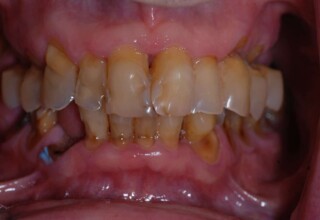

Lower jaw: extractions, direct implant placement and immediate loading (same day) with a transitional bridge.

Upper jaw: Sequential extractions, sequential implant placement and gradual incorporation in the temporary bridge so that the patient was never left without fixed teeth. The aim of the above approach was to have the patient in continuous functional and aesthetic reconstruction, without immediate loading due to anatomical restrictions. Old smiling photos of the patient were used because the natural shape of the teeth was completely lost due to repetitive prosthetic attempts. Tooth relationship and teeth-lip support was transferred to the temporary restorations. Two different transitional bridges were needed to fully estimate phonetics, mastication and esthetics. After the necessary adjustments were finalized, the temporary bridge was used as a guide for the permanent bridges.

Initial

Intermediate

Final